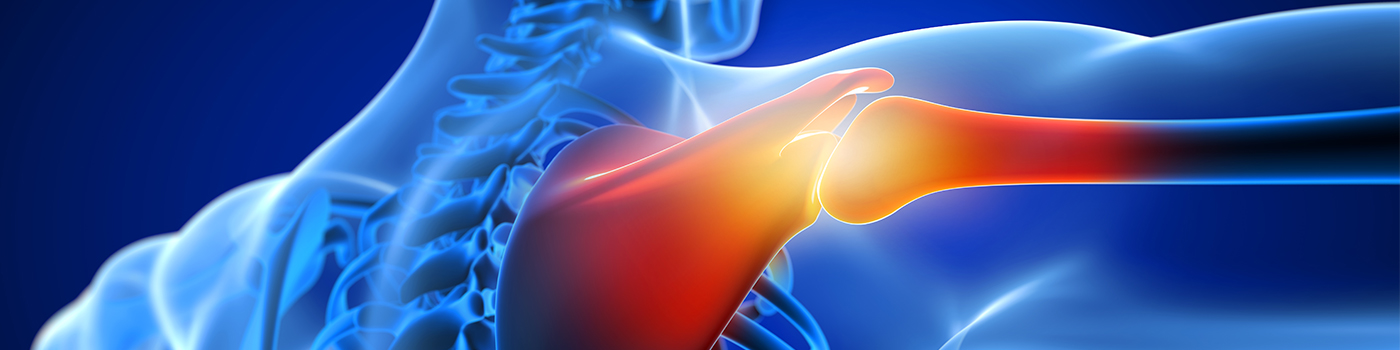

어깨충돌증후군

젊은 나이나 어깨 관절이 건강할 때는 견봉과 어깨 근육 사이의 여유가 충분하지만 나이가 들어 근력이 약해지거나 반복적으로 어깨를 사용했을 때, 외상으로 다쳤을 경우에 견봉과 어깨 근육 사이에 마찰이 일어나 통증을 발생시키는 현상을 말합니다.

어깨충돌증후군은 노화현상에 의한 퇴행성 질환으로 30~40대 이상의 연령층에서 많이 발생합니다.